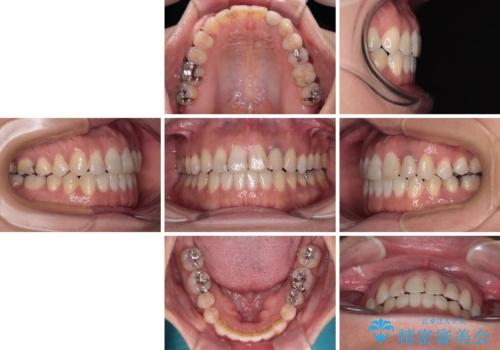

開咬と変色した前歯 インビザライン矯正とオールセラミッククラウン治療

- 前歯の開咬と失活により変色した前歯を気にして来院された患者様です。

開咬の治療は、前歯を閉じるように引っ張り出すよりも、上下臼歯を圧下(骨内にめり込ませる)させることで進める方が長期的に安定した歯列を維持できます。

インビザラインは臼歯の圧下を効果的に行えるため、インビザラインを用いて矯正治療を行うこととしました。

矯正治療が概ね終了した時点で前歯をオールセラミッククラウンにて補綴治療を行い、その後インビザラインにて細かい部分を仕上げていくことしました。

オープンバイトは舌の突出癖により誘発され、治療後も突出癖が残っている容易に後戻りしてしまいます。

治療期間を短縮するためにも、舌突出癖の改善が極めて重要となります。